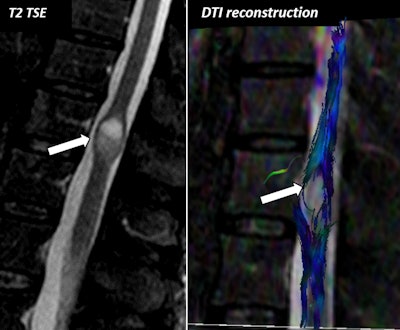

"DTI reconstructions allow us to obtain a 3D representation of muscle fibers and can be used as a complementary tool for skeletal muscle qualitative assessment," Martín Noguerol and colleagues noted. "Nowadays, there is not a clear indication of how or when DTI studies should be performed for skeletal muscle evaluation."

In their second poster, the investigators reviewed the physical basis of DTI and their technical adjustment for spinal cord evaluation. They discussed the biological meaning of parameters derived from DTI studies in the spinal cord and showed the potential applications of DTI for spinal cord evaluation in various clinical settings.

DTI provides both valuable qualitative and quantitative information for spinal cord assessment that can be used as a complementary tool for conventional MRI spinal cord examinations, and it can help to confirm, rule out, and even detect pathology in patients with apparent normal morphological studies and persistence of clinical symptoms. However, the integration of DTI as another sequence in routine protocols for spinal cord assessment is unclear, and specific technical adjustments must be considered prior to acquiring DTI studies for spinal cord assessment.